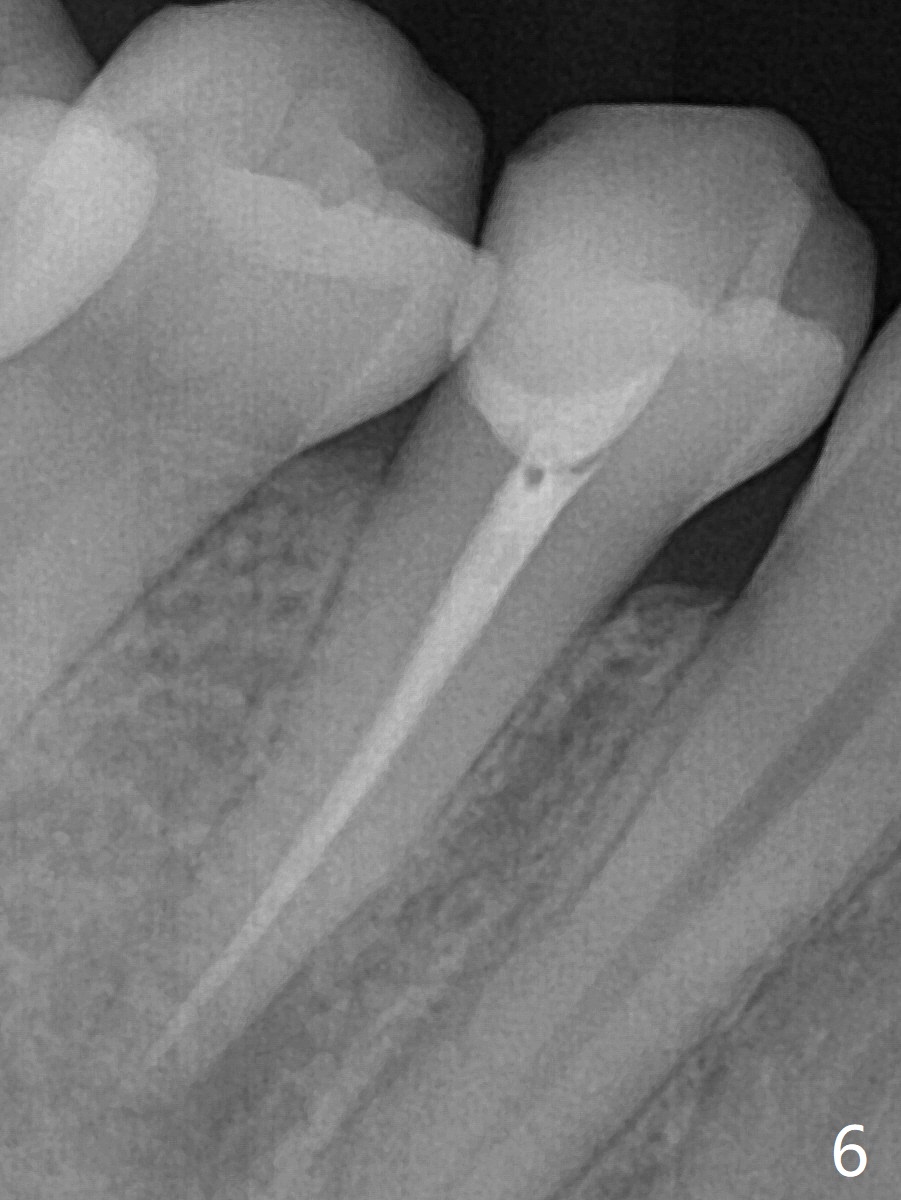

25岁硕士生,女,要求右下4补牙(图一:第一前磨牙),经过解释,欣然接受根管治疗。后者要领基本四条:无菌,根管笔直通畅,使用根尖定位仪和旋转式锥形扩大针和锥形牙胶尖。为了无菌,局麻后常规使用橡皮障(图二 *)。防止断针,尤其是旋转式锥形扩大针,根管治疗开口尽量大(图二箭头),保持扩大针笔直。开始根尖定位仪有点毛病,使用15号锉测定根管长度,不小心超越根尖大约3毫米(图三)。后来倒退4毫米,并得到根尖定位仪证实,主牙胶尖(30/.06)好像长度合适(图四),反复冲洗,最后再插入一个细牙胶尖一次性完成根管治疗和补牙(图五,六)。